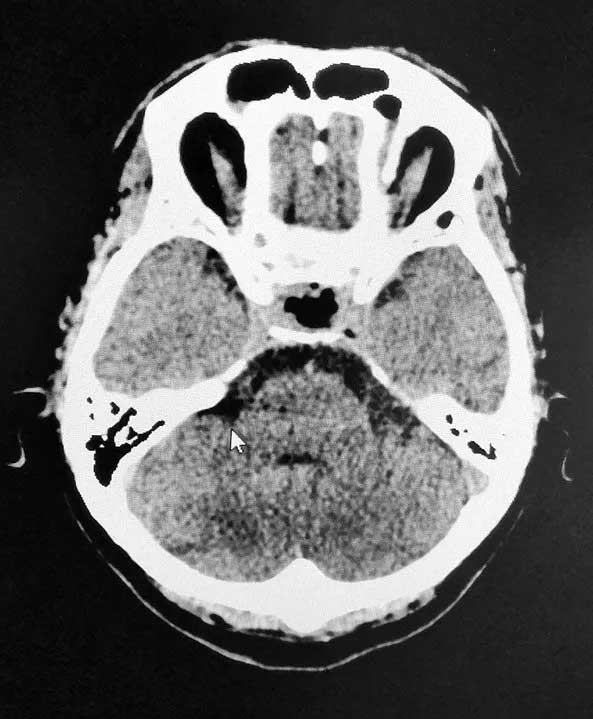

▲ 術后影像,腫瘤被切除